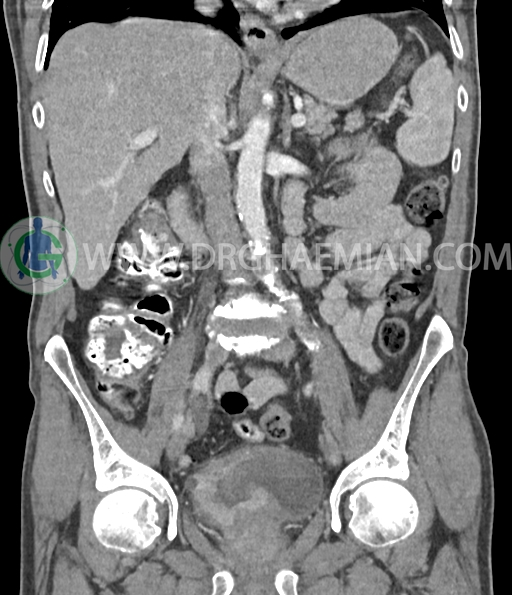

در سی تی اسکن اسپیرال شکم و لگن با و بدون کنتراست خوراکی و وریدی (مولتی دیدکتور 16 با مقاطع ظریف و بازسازی های ساژیتال و کرونال) :

ضایعه کبدی هیپودنس بسیار کوچک به قطر 6mm در سگمان 7 لوب راست کبد مشهود است که با توجه به سایز بسیار کوچک ان در سی تی اسکن به خوبی کارکتریزه نمی شود.

تصویربرداری هایfollow upجهت رد کردن متاستاز توصیه می شود.

کلسیفیکاسیون دیواره ائورت مشهود است.

پروستات با دیامتر عرضی 60mmبزرگ تر از نرمال، همراه با bulging لوب مدین به کف مثانه رویت شد.

افزایش ضخامت جداری و نامنظمی و لوبولاسیون همراه باenhancement مطرح کننده انفیلتراسیون و ضایعات تومورال در سمت راست ناحیه ترایگون و دیواره لترال راست مثانه دیده می شود که باعث اتساع حالب راست و هیدرونفروز moderate در کلیه راست شده است . این یافته های می توانند مطرح کننده TCC باشند .fat stranding در اطراف مثانه مشهود است. بیرون زدگی توده مانند به قطر 18mm در سمت راست ناحیه ترایگون دیده می شود که می تواند مطرح کننده گسترش اکسترا وزیکولر تومور باشد . لنفادنوپاتی با SAD=10mm درlevel ایلیاک داخلی چپ رویت شد . لنف نود دیگر با SAD= 5mm در همین ناحیه مشهود است. با توجه به این یافته ها stage احتمالی تومور T3، N1 or N2 می باشد .